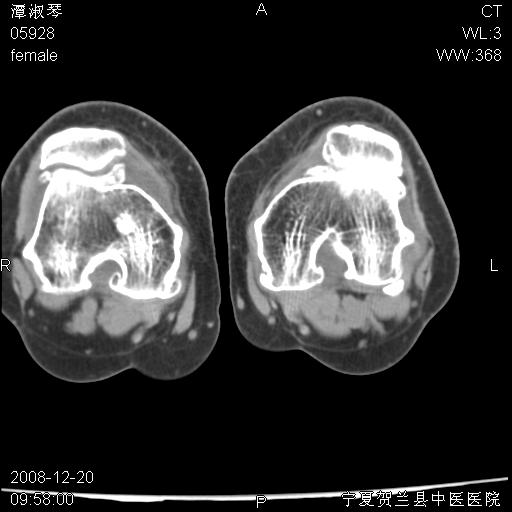

标题: CT17526:请各位看看是啥?

支持骨梗死,退行性骨关节病,膝关节积液.

考虑骨梗死可能性大

骨梗死可能性大

左股骨下段骨梗死。双膝退变。

左胫骨下端松质骨及髓腔内可见点片状高密度灶,骨皮质无明显膨胀及变薄。病变范围较长。支持骨梗死,退行性骨关节病,膝关节积液